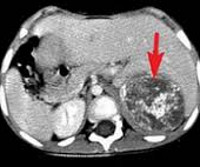

План инструментального обследования в зависимости от локализации нейробластомы может включать в себя КТ, МРТ и УЗИ забрюшинного пространства, рентгенографию и КТ органов грудной клетки, МРТ мягких тканей шеи и другие диагностические процедуры. При подозрении на отдаленное метастазирование нейробластомы назначают радиоизотопную сцинтиграфию костей скелета, УЗИ печени, трепанобиопсию либо аспирационную биопсию костного мозга, биопсию кожных узлов и другие исследования.